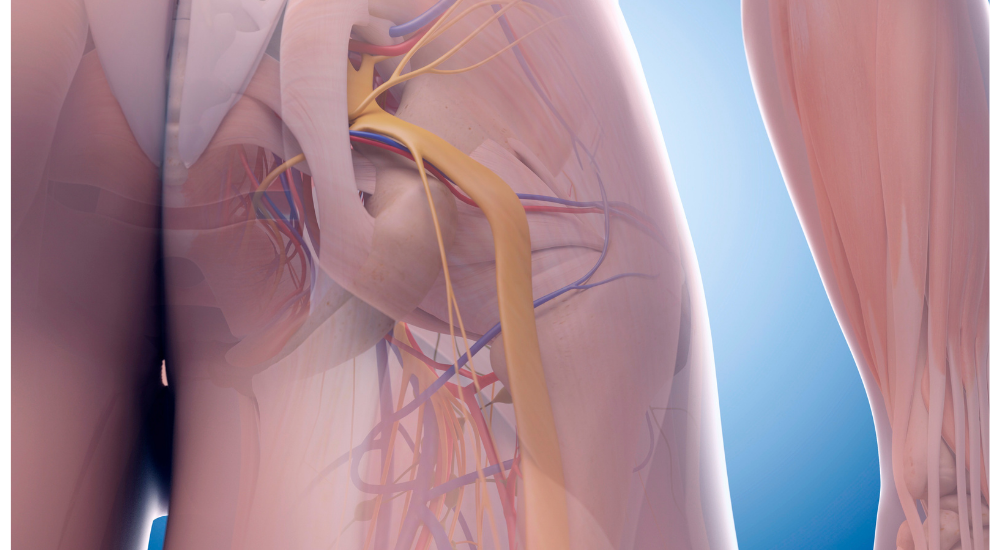

筋膜は、筋肉だけでなく、骨や内臓、神経、血管など、身体のあらゆる構成要素を包み込み、それぞれの場所につなぎとめている、非常に薄い網状の結合組織です。

全身タイツのように身体全体を覆っており、各組織がスムーズに滑り合うための潤滑油のような役割や、組織同士の隔壁となる役割、さらには姿勢の保持や、力(張力)を全身に伝える役割も担っています。

この筋膜は感覚神経が豊富で、痛みを感知しやすい部位でもあります。

筋膜の機能が低下すると、その中を走る筋肉の動きが制限され、血行が悪くなります。

これにより、筋肉への栄養供給が滞り、疲労物質や痛み物質が蓄積しやすくなります。